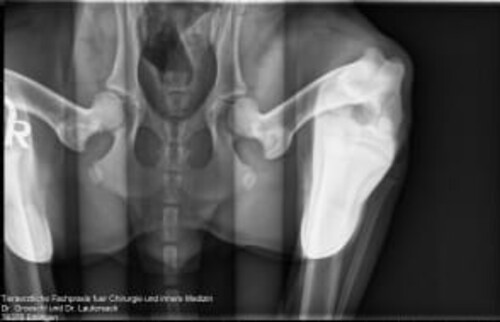

Bilder einer vollständigen Hüftdysplasie-Untersuchung beim Hund

In unserer Tierklinik bei Karlsruhe können unsere Ärzt*innen durch die Aufnahmen eine zuverlässige Prognose für die Weiterentwicklung der Hunde-Hüfte stellen.

Schwarz-weißes Röntgenbild der Hüftgelenke und des Beckens eines Hundes in der Aufsicht.

Schwarz-weißes Röntgenbild der Hüftgelenke eines Tieres mit abgespreizten Hinterbeinen.